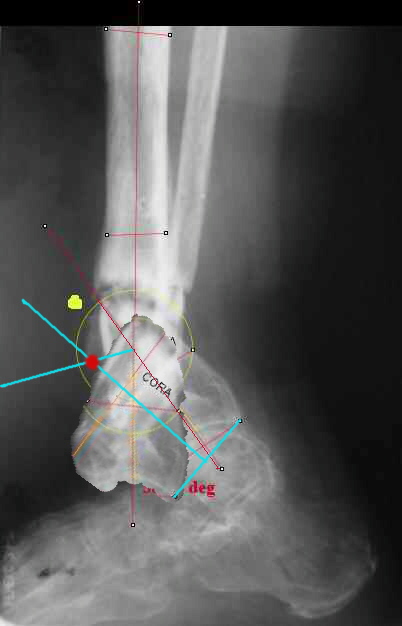

I played with your image using some orthopedic software we have been developing for digital

image analysis.

What you see marked up is the intercept of two mid-line tool centre lines, used to define the CORA. An angle tool gives the angular deformity and a circle tool is applied to show that a correction around the CORA through the old # will restore alignment without much translation.

TDVC> I played with your image using some orthopedic software

TDVC> we have been developing for digital image analysis.

I definitely have to learn more about this. THX in advance.

TDVC> a correction around the CORA through the old # will restore

TDVC> alignment without much translation.

Maybe my "embedded software" is obsolete but it hints me to place hinges at the yellow point - this must result with alignment and some lengthening without translation. What do you think?